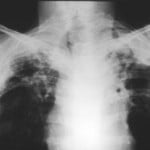

15 mag – Sospetto caso di tubercolosi polmonare segnalato in un alunno che frequenta la scuola Lombardini di Guastalla. A darne notizia e’ l’Ausl di Reggio Emilia che informa che “l’alunno e’ attualmente ricoverato in ospedale in condizioni di salute buone ed ha iniziato la terapia specifica”. Il Servizio di igiene e sanita’ pubblica ha gia’ avviato tutte le procedure previste per l’individuazione dei contatti a rischio, lo svolgimento degli accertamenti sanitari necessari, la sorveglianza sanitaria dei contatti e la comunicazione alle famiglie coinvolte.

La tubercolosi – ricorda l’Ausl – e’ una malattia a prevalente localizzazione polmonare e si puo’ trasmettere da persona a persona per via respiratoria. La trasmissione della malattia avviene attraverso un contatto stretto e molto prolungato con il malato in uno spazio confinato, nei tre mesi precedenti l’esordio della malattia. La trasmissione del microrganismo responsabile della malattia non avviene pertanto con facilita’: sono necessarie particolari condizioni ambientali, condizioni legate alla tipologia della malattia e allo stato immunitario del soggetto esposto.